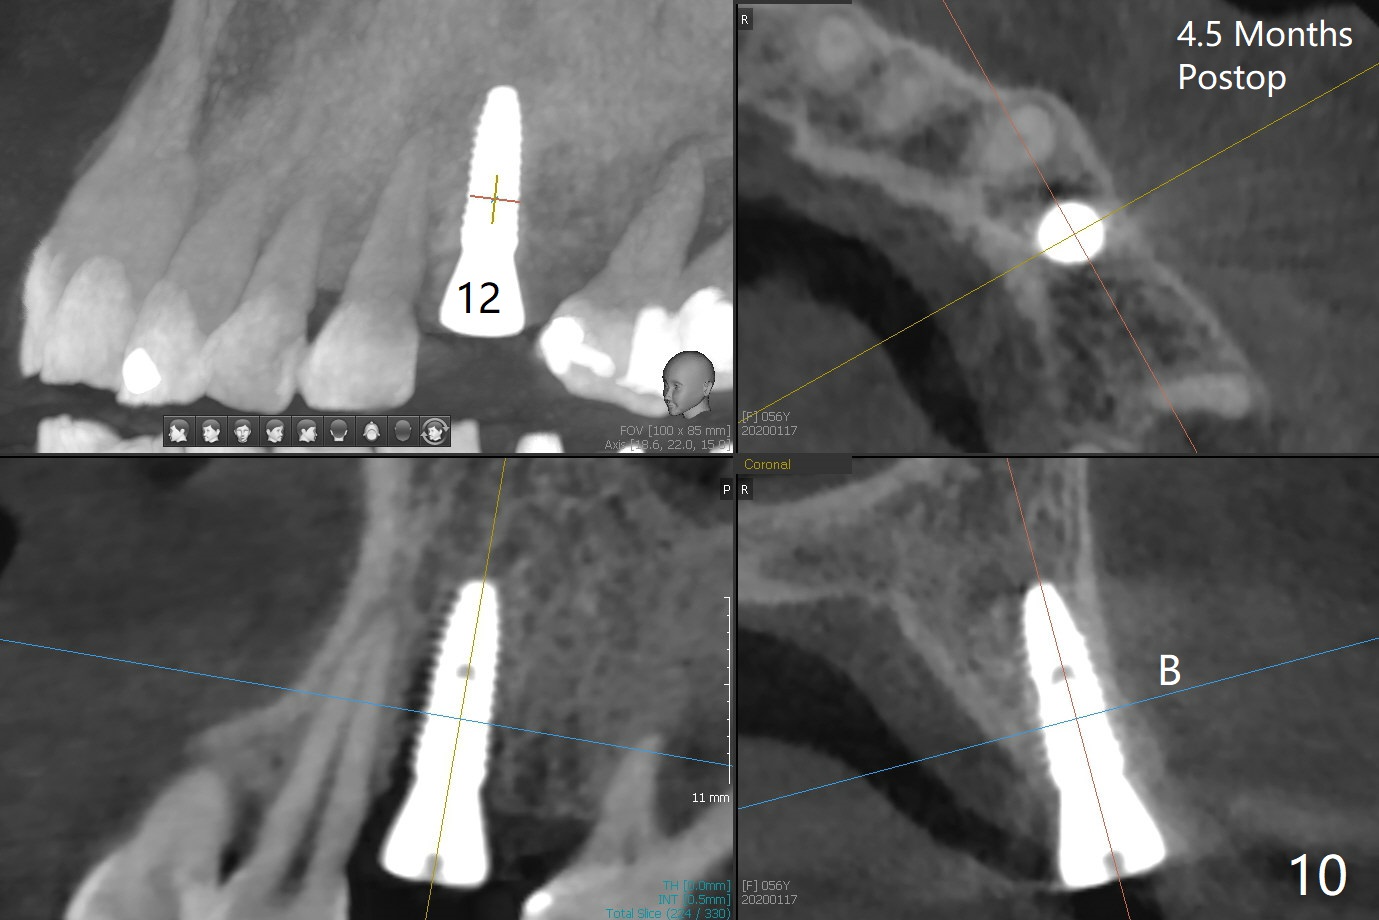

PA is taken after a 2.2 mm drill reaches the depth at #12, since osteotomy is initiated in the mesial slope of the socket (Fig.1 red dashed line) and the neighboring root (*) slightly curves distal. A 8.6x5 mm healing abutment is used to close the socket with the large mesiodistal space after bone graft (Fig.2 *). In contrast, the socket at #20 is large; a 4.5x4.5(3) mm cementation abutment is placed for an immediate provisional to keep autogenous bone (harvested from the site of #18) in place (Fig.3). Six months postop, the patient does not want implant FPD. She wants an additional implant at #19. Since the space between the implants #18 and 20 is 9.41 mm, a narrow implant is indicated (3 or 3.5 mm, Fig.4), in spite of the sufficient buccolingual width (Fig.5). The position and trajectory of the 1.2 mm initial drill and 3x10(2) mm 1-piece implant are acceptable with free hand (Fig.6,7). After 3-4 more turns, panoramic X-ray (Fig.8) and CT (Fig.9) are taken for 28-30 guide. It appears that the 1-piece implant is placed acceptable buccolingual (Fig.9 B). The implants at #12,18,20 (4.5 months postop with guide) are shown in Fig.10-12. It appears that guided surgery is superior in buccolingual position and trajectory to free hand. There is crestal remodeling without implant thread exposure 11 months postop (Fig.13).